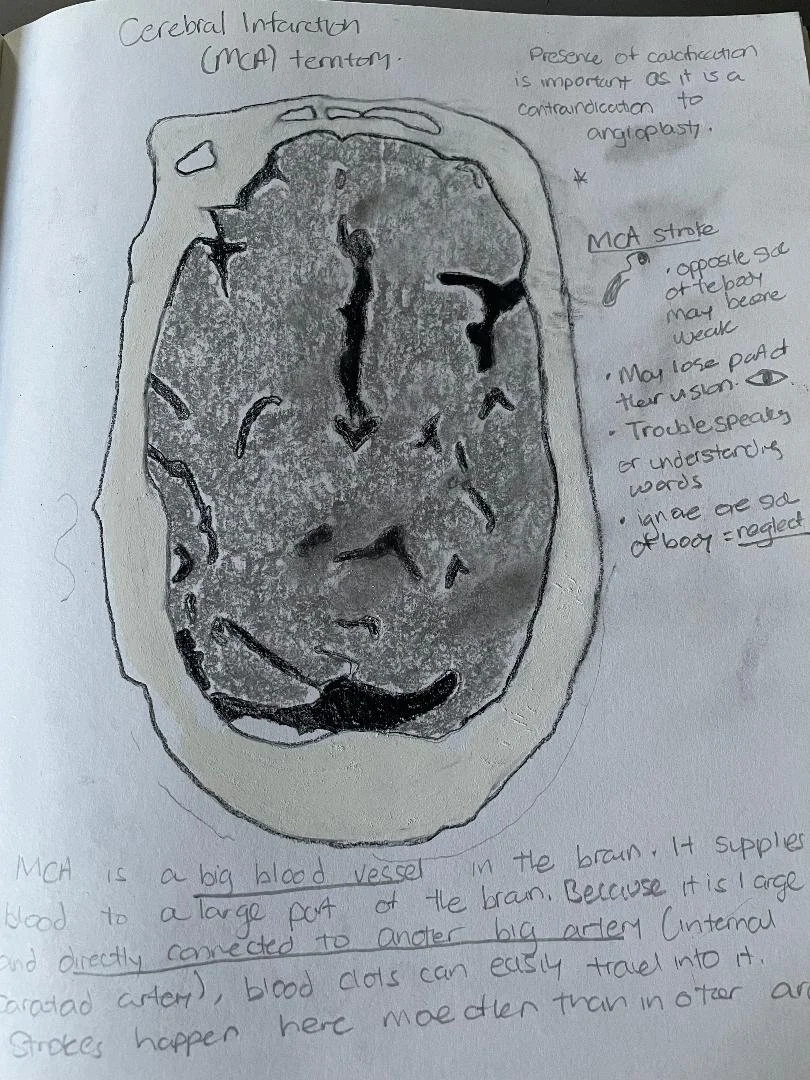

Middle cerebral artery (MCA) infarct